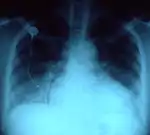

- No morfotipo brevilíneo, indivíduos com o tórax largo, uma distância púbis-pé menor que a distância púbis-vértice, muitas vezes com excesso de peso e um diafragma elevado, o coração está numa posição mais horizontal. O impulso apical é desviado para acima do 4º espaço intercostal e para fora da linha médio-clavicular, na linha axilar anterior e mesmo por vezes na linha axilar média. Numa radiografia do tórax o coração aparece "deitado" sobre o diafragma dando um falso aspecto de dilatação cardíaca porque o índice cardiotorácico (sinal radiológico: razão entre o diâmetro do coração e o diâmetro torácico) está aumentado.[2]

- Na dextrocardia em que a posição do coração é a "imagem em espelho" da posição normal, a ponta cardíaca e as cavidades esquerdas situam-se do lado direito, o impulso apical sente-se na mesma localização descrita mas do lado direito.[3]